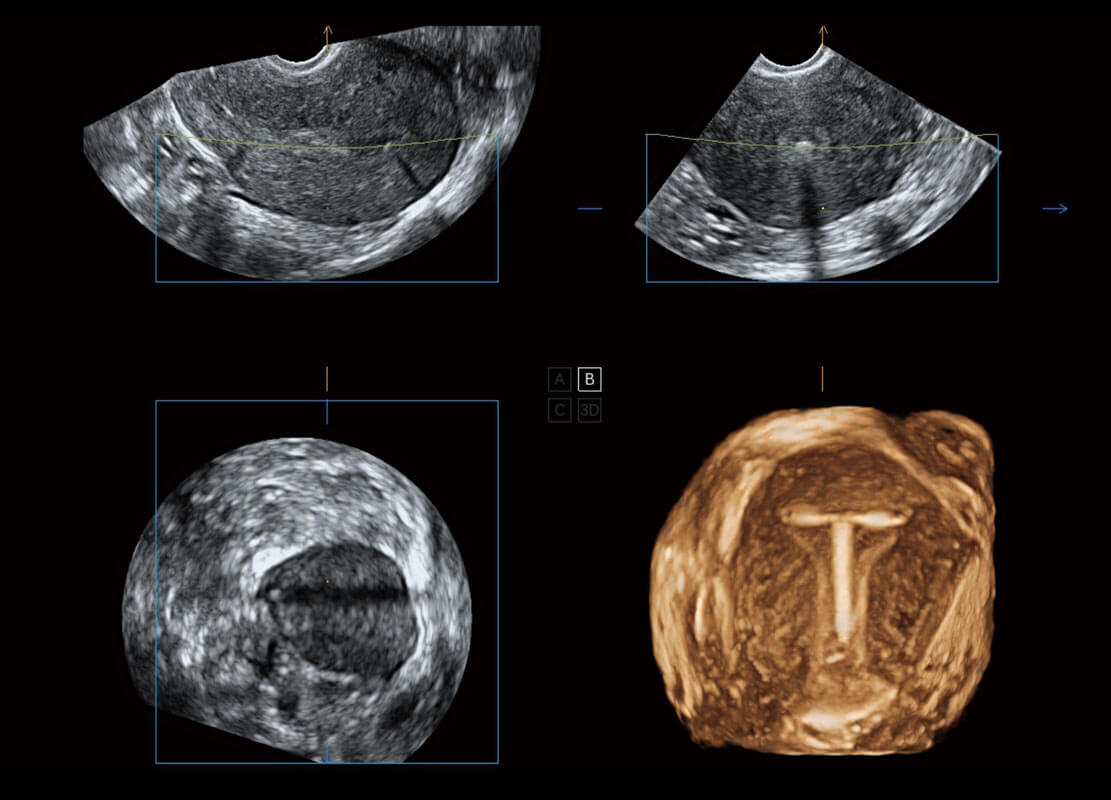

生殖健康

P60优异的图像质量搭载专科探头,在妇科基础疾病的诊断、卵泡生长的监测、输卵管通畅情况的判别等方面为您提供生殖应用方案。

• 腔内三维-宫内节育器

• 腔内三维-光影成像